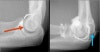

팔꿈치 관절의 MRI 단면 영상

2) Radial head for radiographically occult fractures